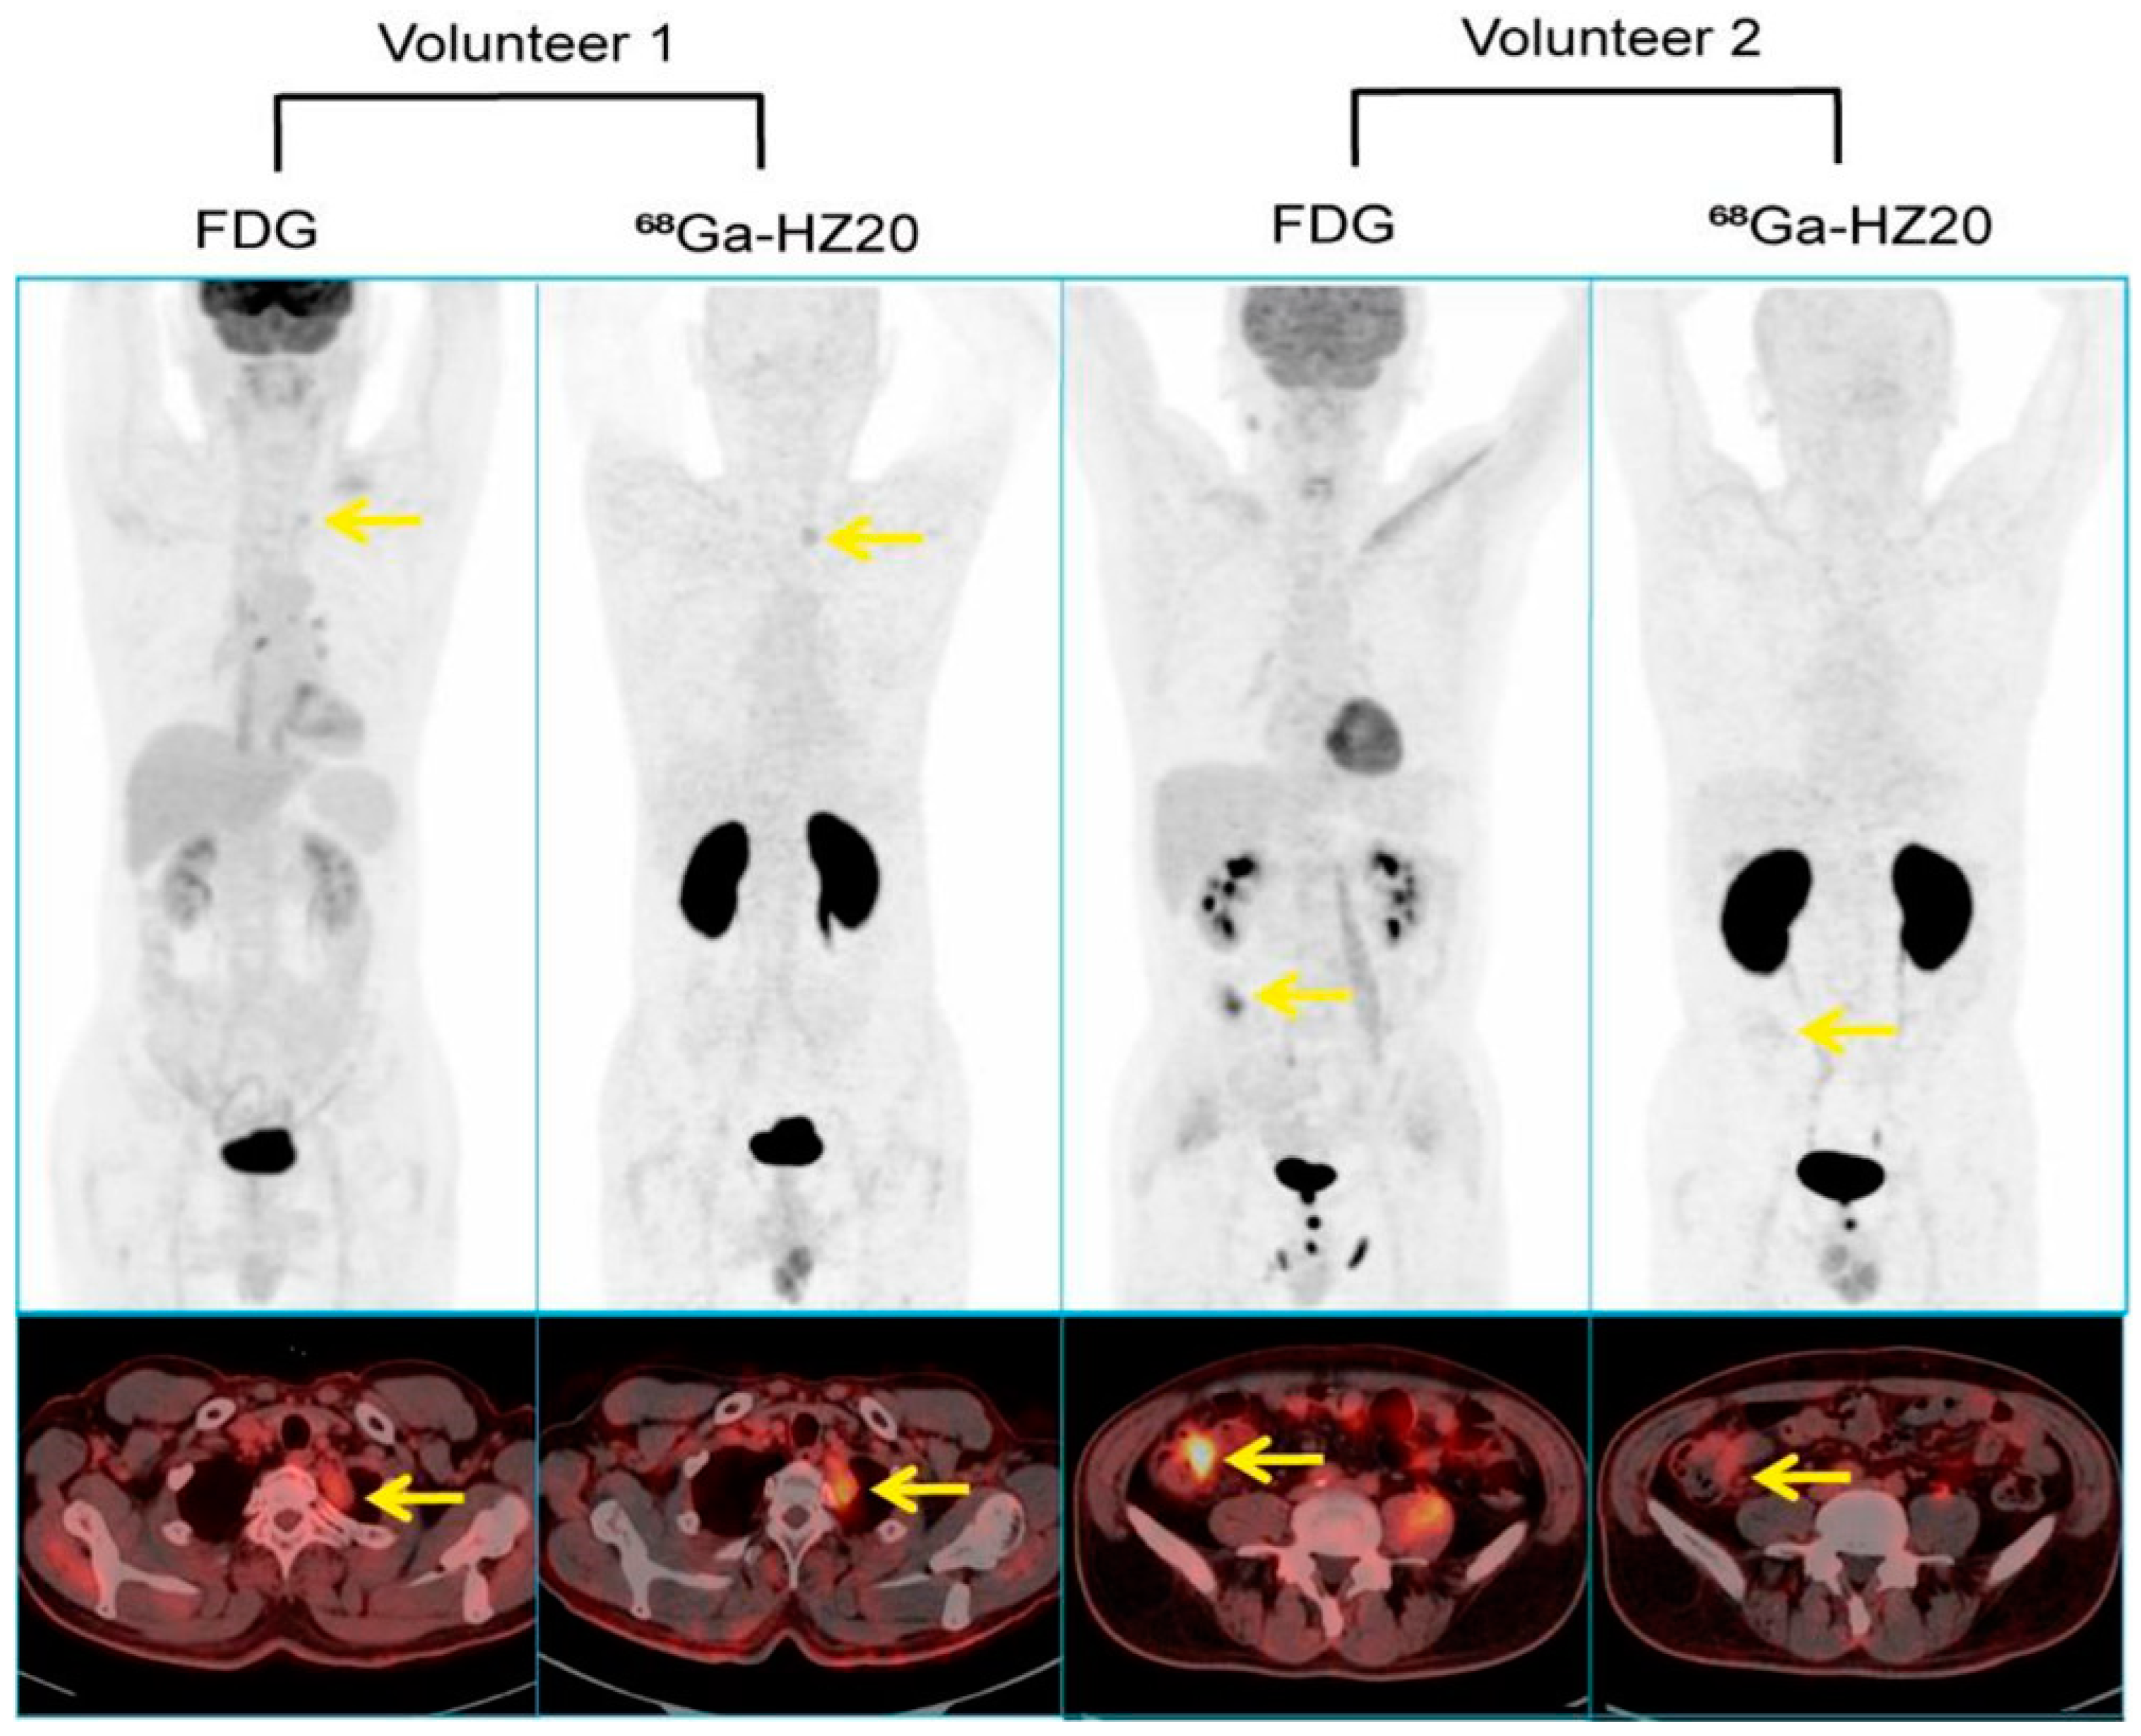

6. ACE2 Imaging in Cancerous Tissues

- Zhang, Q.; Liu, T.; Ding, J.; Zhou, N.; Yu, Z.; Ren, Y.; Qin, X.; Du, P.; Yang, Z.; Zhu, H. Evaluation of (68)Ga- and (177)Lu-Labeled HZ20 Angiotensin-Converting Enzyme 2-Targeting Peptides for Tumor-Specific Imaging. Mol. Pharm. 2022, 19, 4149–4156. [Google Scholar] [CrossRef]